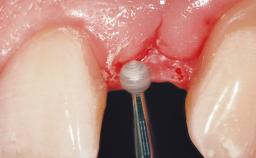

Immediate Flapless Placement of an Implant in a Maxillary Left Central Incisor Site

A 42-year-old female patient was referred to our clinic at the School of Dentistry of the University of São Paulo in November 2004, presenting a deficient restoration in the upper left central incisor. The clinical examination revealed no gingival retraction or any signs of gingival inflammation and, therefore, previous periodontal treatment was not considered. The patient presented a high lip line at full smile and a thin tissue biotype. This combination characterized a high-risk situation from an anatomic point of view, which required careful preoperative planning and cautious surgical execution.

Lip Line No exposure of papillae Exposure of papillae Full exposure of mucosa margin

Periodontal Phenotype Low-scalloped, thick Medium-scalloped, medium-thick High-scalloped, thin

Soft Tissue Anatomy Intact Defective